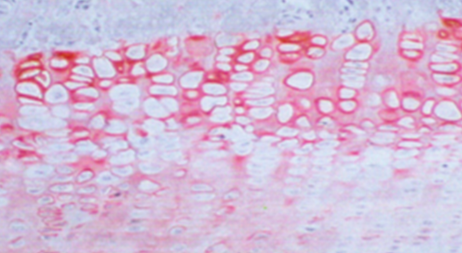

Uroplakine II

Les Uroplakines Ia, Ib, II et III sont des protéines structurales des cellules urothéliales différenciées en position terminale.

Dans les cellules urothéliales non néoplasiques, les Uroplakines sont exprimées dans la membrane luminale des cellules superficielles.